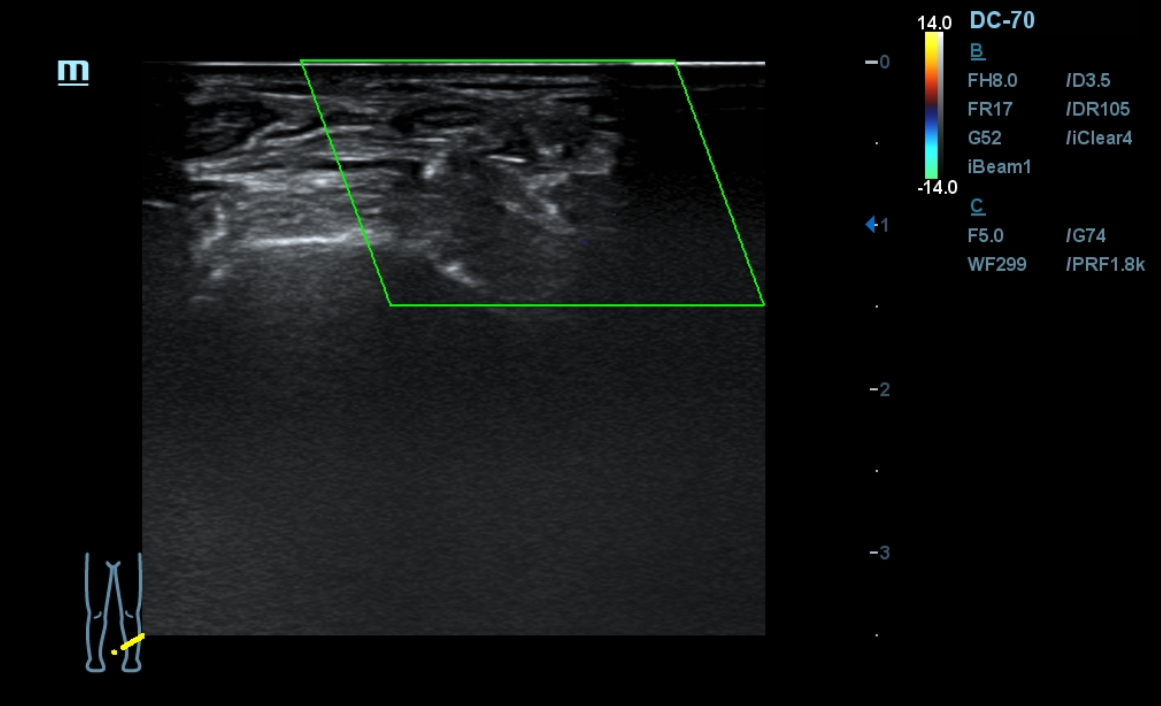

Ante los antecedentes patológicos de nuestro paciente, junto con los hallazgos relevantes de la anamnesis y exploración física decidimos realizar una ecografía clínica de miembros inferiores. En la arteria femoral común el flujo está presente. En la arteria femoral superficial se observa una obstrucción total. Así mismo, en un corte longitudinal de la arteria poplítea y tibial observamos una obstrucción total.